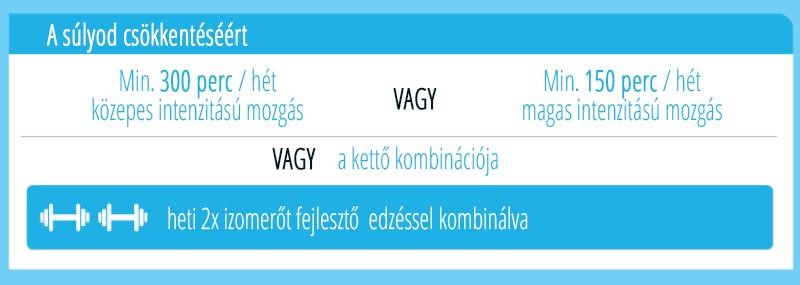

Az edukáció olyan fontos kérdéseket érint, mint: mi számít meddőségnek, mikor érdemes szakemberhez fordulni, hogyan hat az életkor a termékenységre, illetve milyen kockázatot jelentenek a szexuális úton terjedő fertőzések. Az iránymutatás külön kitér a legfontosabb kockázati tényezőkre, mint a dohányzás, a túlzott alkoholfogyasztás, az elhízás vagy éppen az alultápláltság, melyek mind kedvezőtlenül hathatnak a reproduktív egészségre. Ezzel szemben a kiegyensúlyozott, tápanyagokban gazdag étrend, a rendszeres testmozgás, valamint a dohányzás elhagyása bizonyítottan hozzájárulhat a termékenység megőrzéséhez és a későbbi problémák megelőzéséhez.